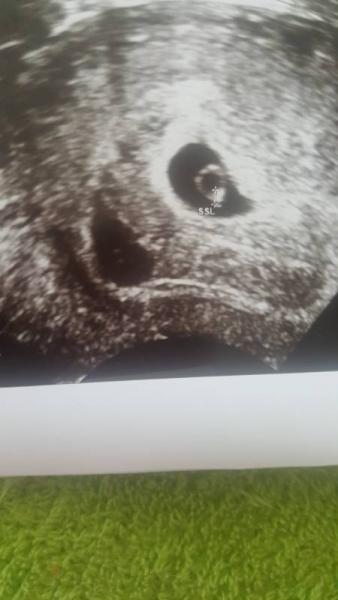

Bin neu hier 36 Jahre und bin in der 6 woche habe ab und zu blutungen liege viel und habe eine neues Bild bekommen und bin voll verwirrt vieleicht könnt ihr mir einen rat oder so geben Gruss sabrina

Bild zu Vielleicht kann mir jemand helfen - Schwanger - wer noch? Rund um die Schwangerschaft

Hallo erstmal weil meine Ärztin nicht weiß wo die blutungen her kommen deswegen habe das Bild zu gemacht sind es 2 Baby da meinte sie ich soll warten

Wuerde sagen 2

Ich auch aber warum sieht man bei dem einen noch nichts ausser einen Punkt hab halt leichte blutung manchmal weniger manchmal bisschen mehr ich habe noch 2 kinder ist nicht so einfach als zu liegen

Sieht aus als wären es 2 das andere nur nicht so weit entwickelt?

Oder könnte es sein das das andere was nicht so entwickelt ist vieleicht abgegangen ist und ich deswegen leicht blute aber dann wäre doch die fruchthöhlen nicht mehr da oder

Das sind 2 Fruchthoehlen. Aber zu der Zeit kann es leider auch sein, dass sich nur eines (oder leider auch keins) weiterentwickelt. Zu den Blutungen: Da sie nicht sehen kann, woher die Blutungen kommen, ist das schonmal positiv! Denn wuerden sie von den Fruechthoehlen kommen, wuerde sie das sehen und dann sehe es auf jeden Fall schlecht aus. Bei mir traten Blutungen von der 7. - 9. SSW auf. Erst spaet sah man, dass es von einem kleinen Haemtom kam. Alles Gute!